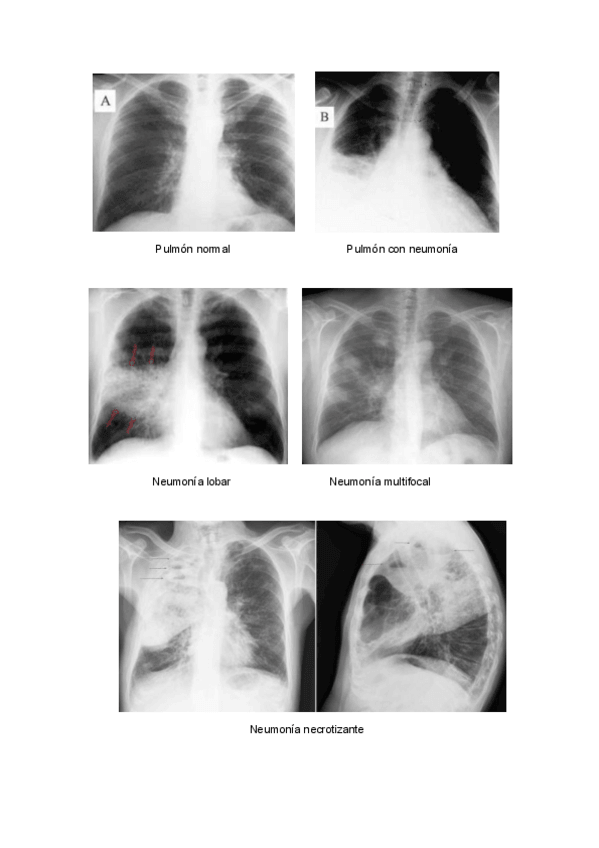

He publicado nuevos apuntes de 2º Enfermería en alteraciones de la salud I: NEUMONIA.pdf

4 páginas